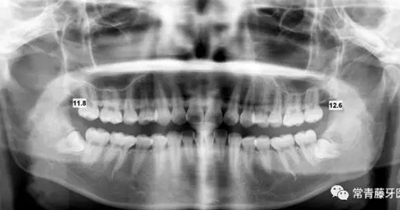

影像學(xué)檢查

曲斷顯示38、48阻生;雙側(cè)TMJ髁突頭略不對稱。

頭影測量顯示上下頜骨發(fā)育不足,且呈現(xiàn)骨性Ⅱ類。

曲斷可見牙根基本平行。

(3)全牙列遠(yuǎn)移種植釘植入位點(diǎn)為上頜第一磨牙根上方顴牙槽嵴處,使其與牙根平行,在術(shù)前需CBCT確認(rèn)骨量,否則有脫落或無法植入的可能。